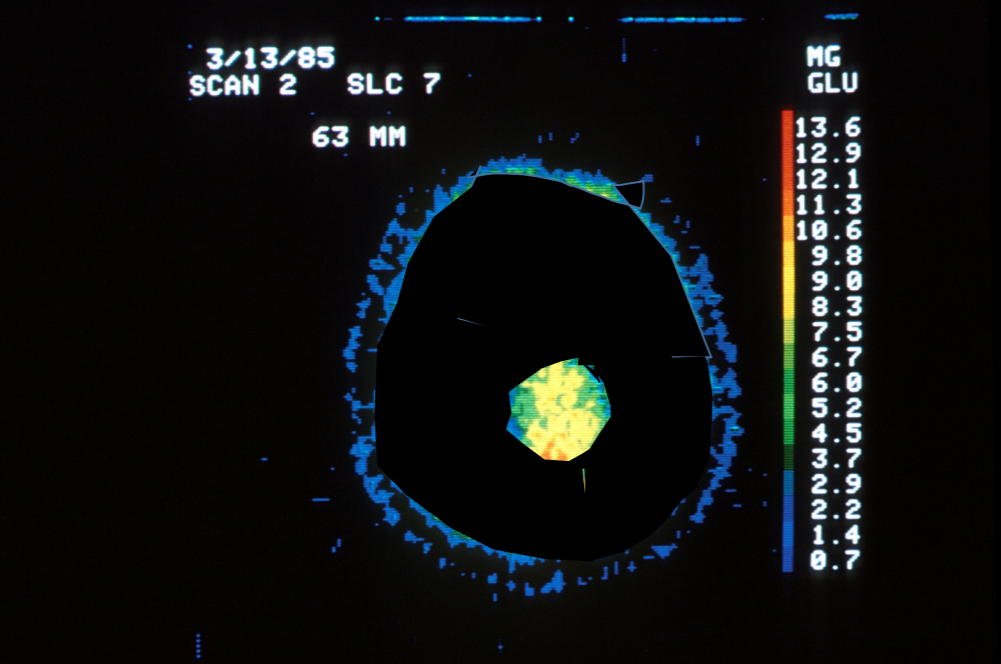

Ciekawą symulację opublikowało czasopismo „Psychological Science” (Stephen Chew). Do zilustrowania tego mitu wykorzystano rzeczywisty skan mózgu, wykonany przy użyciu PET (pozytronowej tomografii emisyjnej, dzięki której możemy zobaczyć – w dużym uproszczeniu – ile glukozy zużywają poszczególne obszary mózgu).

Źródło: „Psychological Science”

Na zdjęciach widoczny jest skan mózgu odpowiadający 10% jego aktywności. Jest to barwny wycinek – im cieplejszy odcień, tym większe zużycie glukozy, czyli większa jego aktywność. Czarne tło, oznaczające brak aktywności, zajmuje 90% obrazka.